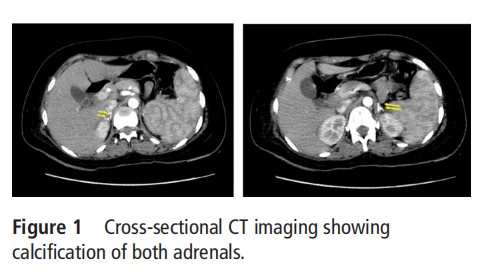

A woman in her 20s presented to us with repeated episodes of giddiness and hypotension requiring multiple hospitalisations in the preceding year. She had an episode of severe abdominal pain followed by a history of easy fatigability, anorexia and progressive hyperpigmentation associated with a weight loss of 5kg over the past 1year. On clinical examination, there was diffuse hyperpigmentation and her blood pressure was 90/50mm Hg with a significant postural drop. The rest of the systemic examination was normal. Blood investigations revealed low sodium(125 mmol/L), hyperkalaemia (5.5 mmol/L), hypocortisolemia(8:00 am cortisol of 2ug/dL) and an elevated plasma adrenocorticotropic hormone(ACTH) of >1250 pg/ml. Přítomnost nízkého sérového kortizolu v přítomnosti zvýšeného ACTH naznačovala primárnínedostatek adrenalinu. Následně bylo provedeno CT vyšetření břicha k zobrazení nadledvinek, které ukázalo bilaterální mohutné kalcifikace zahrnujícínadledvinekžlázyna obou stranách naznačuje výskyt předchozího krvácení do nadledvin (obrázky 1 a 2). Dále bylo provedeno etiologické vyšetření, které prokázalo normální protrombinový čas a prodloužení trvání aktivovaného tromboplastinového času (59s), které se nekorigovalo přidáním normální plazmy. Byl jí diagnostikován antifosfolipidový (aPL) syndrom na základě přítomnosti lupusových antikoagulačních a antikardiolipinových protilátek a protilátek proti beta 2 glykoproteinu 1. Další provedené krevní testy zahrnovaly kompletní hemogram, který ukázal hemoglobin 10 g/dl(N: 13-15g/dl), celkový počet leukocytů 7100/mm3 (N:4000-11000/mm³, průměrný korpuskulární hemoglobin byl 25,2 pg, počet retikulocytů 3,09 procenta, diferenciální počet ukázal 77 procent neutrofilů, 1 % eozinofilů, 13 % lymfocytů a 9 % monocytů Počet krevních destiček byl 1,52 lakh/mm².D-dimer byl 233 ng/ml. U této pacientky nebyly k dispozici testy na fibrinogen a agregaci krevních destiček.Zahájila léčbu hydrokortisonem a fludrokortizonem.Pro APS byla zahájena léčba enoxaparinem a poté překryta warfarinem.